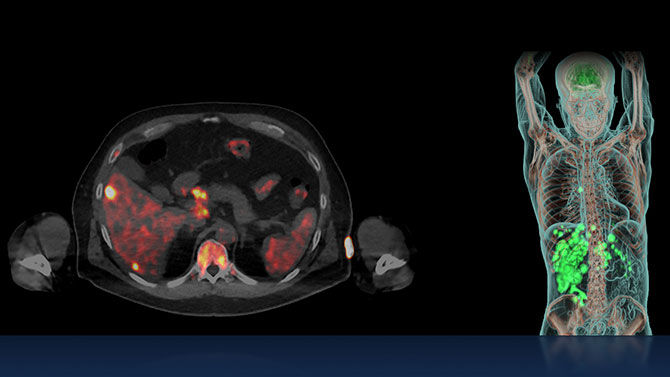

The approach of zeroing in on tumor receptors with positron- and gamma-emitting radioligands to visualize cancer cells, and beta- or alpha-emitting radioligands to destroy cancer cells makes theranostics the quintessential targeted care pathway.

Radioligand therapies have historically been one of the last treatments for cancer, but new evidence shows positive results if this type of care is used earlier, closer to when cancer is diagnosed.² Because of the limited side effects of this precision treatment, it is now a pre-chemo therapy option for some patients.

Already chosen to treat patients with mCRPC, neuroendocrine tumors, thyroid and other cancers, researchers are exploring⁵ a wider range of cancers, such as brain, breast, pancreatic, and ovarian, that may be treatable with radioligand therapies in the next five to ten years.

Radionuclides like ¹⁷⁷Lu, ¹³¹I, and ⁹⁰Y have established themselves as effective cancer treatments.⁶ In the next few years, researchers are working to add several more radionuclides to the fight against cancers, including two alpha-emitting candidates, ²¹²Pb and ²²⁵Ac.⁵

Digital CZT SPECT/CT is a major enabler in theranostics. With the ability to identify the bio-distribution and perform dosimetry for therapies like ¹⁷⁷Lu, pioneering clinicians rely on SPECT/CT to monitor therapy.